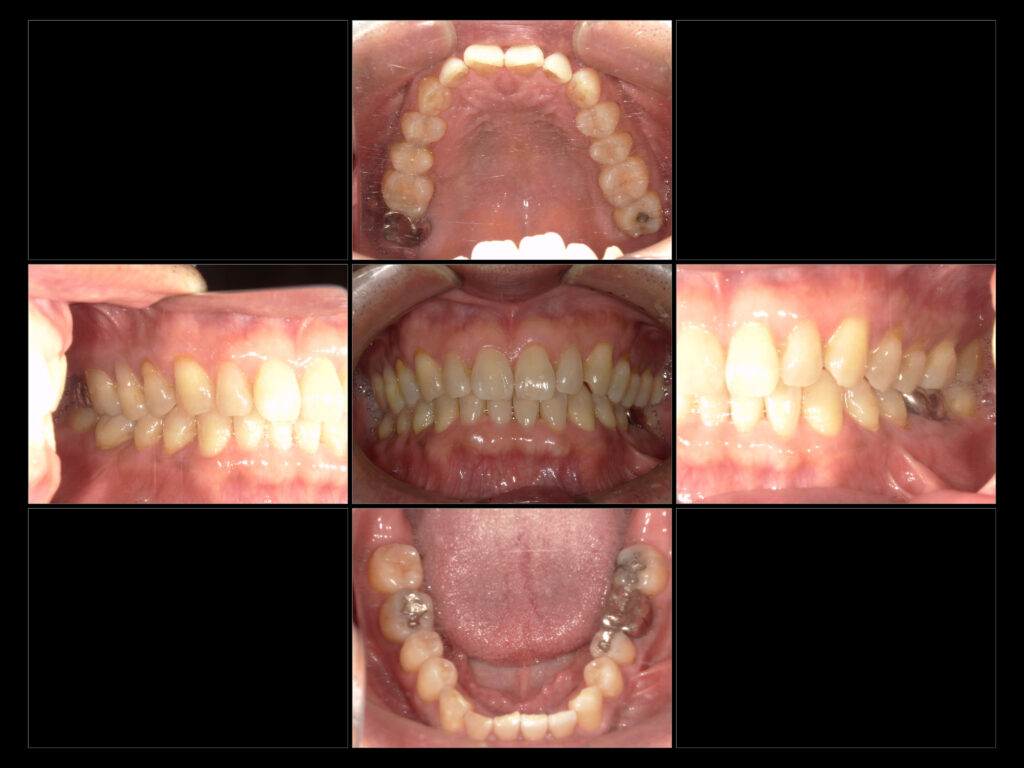

↑ R7 1/7 初診時口腔内写真

●主訴 右上奥20年前に抜歯したところが腫れてる気がする

左下奥かぶせ物に物詰まる

●治療内容 左下6インプラント

左下57右下6 e-maxIn

●年齢 68歳

●性別 男性

●治療期間 1年2ヶ月 現在メインテナンスで経過観察中

●費用 764,500円